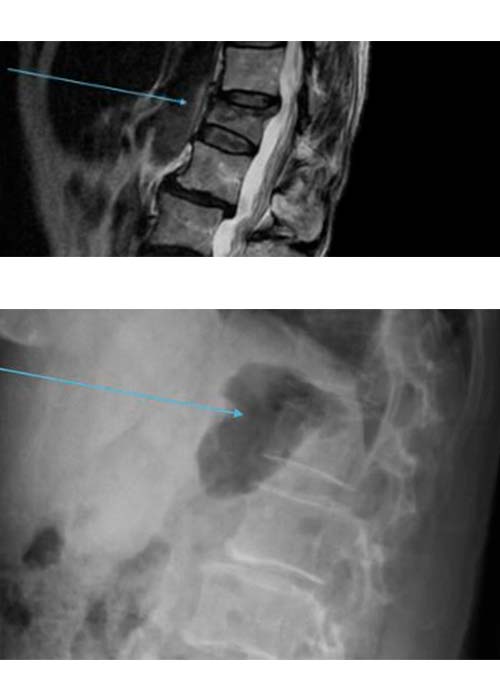

Preoperatorio

Una vez realizadas las pruebas de imagen, estas muestran una fractura acuñamiento de la 1º vértebra lumbar L1 sin que se vea afectado el muro posterior y con signos de edema agudo. Se decide realizar una cifoplastia.